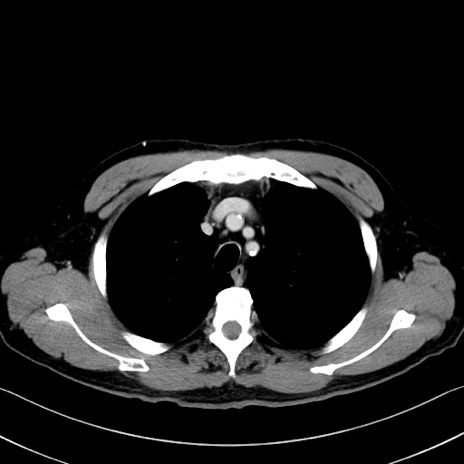

症例35(横断像)

【症例】70歳代 男性

【主訴】腹部膨満、嘔吐

【現病歴】昨日より腹部膨満感出現。本日増悪し、仙痛出現。嘔吐あり、受診。

【既往歴】糖尿病、胆摘後

【身体所見】BP 149/80mmHg、HR 74/min、BT 35.9℃、腹部:膨満、軟、圧痛なし。腸雑音減弱あり。上腹部正中切開瘢痕あり。

【データ】WBC 13500、CRP 1.72